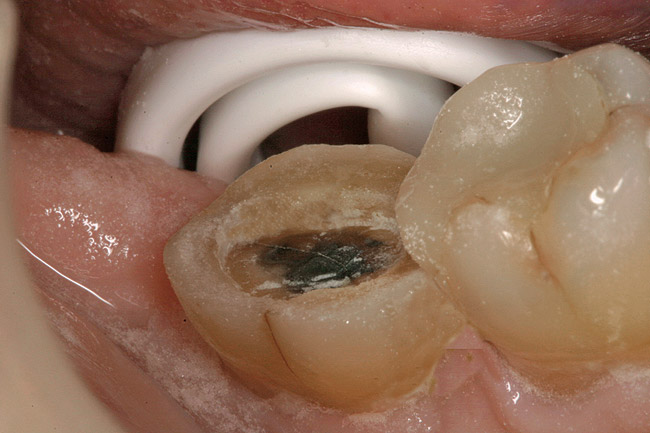

A 70-year-old patient presented with symptoms of a cracked tooth scenario, with intermittent pain upon chewing and thermal sensitivity. The diagnosis was supported through various tests, which determined the lower right second molar had an incomplete fracture that extended from the distal marginal ridge to the mesial marginal ridge. After treatment options were presented, an all-ceramic restoration was decided upon. The tooth was prepared for a nonretentive, adhesively retained all-ceramic restoration ("table top" preparation) (Figure 2 and Figure 3). After the preparation was completed a mild self-etching adhesive was applied to the dentin according to the manufacturer's instruction (Figure 4). There was little concern, if any, of the adhesive reaching the band of exposed enamel. The adhesive was light-polymerized for 5 seconds to secure the layer to the dentin (Figure 5). To eliminate the oxygen-inhibited layer a water-soluble gel was applied to the adhesive and further light-polymerization was completed (Figure 6 and Figure 7). For direct digital scanning cases in which a powdering technique is employed for image capture, it may be more difficult to remove the powder after scanning if the oxygen-inhibited layer is still present.

Figure 3  Facial view (Fig 2) and occlusal view (Fig 3) of nonretentive adhesively retained ("table-top") preparation.

Figure 3

Figure 4  Application of a self-etching adhesive immediately after completion of tooth preparation.

Figure 4